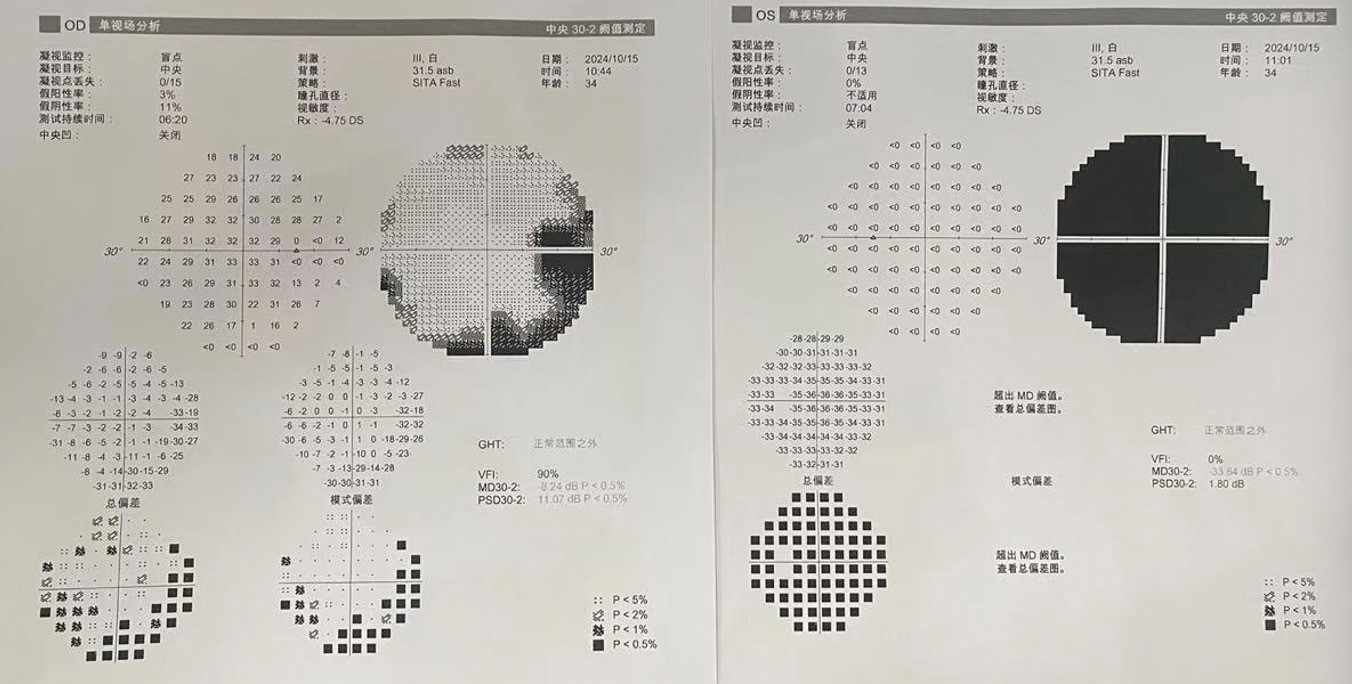

入院查体:神志清,精神可,言语流利,左侧瞳孔4mm>右侧瞳孔3.5mm,右侧对光反射存在,间接对光反射消失,左侧直接对光反射消失,间接对光反射存在,左眼失明,右侧鼻唇沟浅,四肢肌力及肌张力大致正常,双侧巴氏征未引出,颈软。

前颅窝底脑膜瘤常起源于前颅底筛骨筛板处的硬膜,瘤体多为双侧生长,少数为偏侧生长,女性稍多于男性。肿瘤可累及鸡冠和蝶骨平台的任何区域,是前颅窝肿瘤中最多见的一种。因为肿瘤位于前颅窝底,额叶在功能上属于“哑区”,患者就诊发现肿瘤时瘤体多已巨大。主要症状可有颅内压增高症状、视力减退、癫痫以及精神症状等。该患者主因“左眼失明10个月,头痛3个月”就诊。术中采用双额冠状开颅,左侧为主,由于肿瘤体积巨大,术中切除少许薄层额叶脑组织,边离断基底、边瘤内减压,分块切除肿瘤,最终探查肿瘤基底主要位于鸡冠、筛板、蝶骨平台、鞍结节、前床突处硬膜,术中见肿瘤供血主要来源于前颅窝底硬膜及大脑前动脉分支,术中仔细辨认供血动脉、过路血管,大脑前动脉及其分支保护完好,术中见视神经、视交叉受压明显,尤其是左侧视神经已缺血苍白,最终达Simpson II级切除。术者体会,该患者术前行多模态重建,可见瘤表数条粗大的静脉,术中切莫过早离断肿瘤的引流静脉,以防因引流不畅致瘤体肿胀出血;术前行多模态重建,利于鉴别供血动脉、过路血管,早期离断供血动脉更利于肿瘤切除;该类肿瘤基底一般较为广泛,不能盲目离断基底,尤其是近鞍结节处,可以于中线处离断基底,进入第一间隙后向两侧探查并保护视神经,待充分缩小瘤体看清楚毗邻的血管神经后再将其完全切除;术毕做好多层颅底重建以防脑脊液漏。另外,该患者术前左眼失明已达10个月,术后第1天即有光感,术后1月复查左眼视力可达50cm内数指,这在临床中非常少见,对于此类病人,不要轻易放弃挽救视力的任何机会。